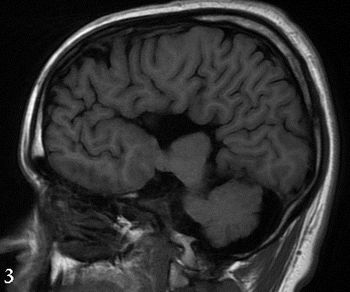

A rare finding is a timely lesson for all clinicians who are touched in one way or another by the injectable drug crisis in the US.